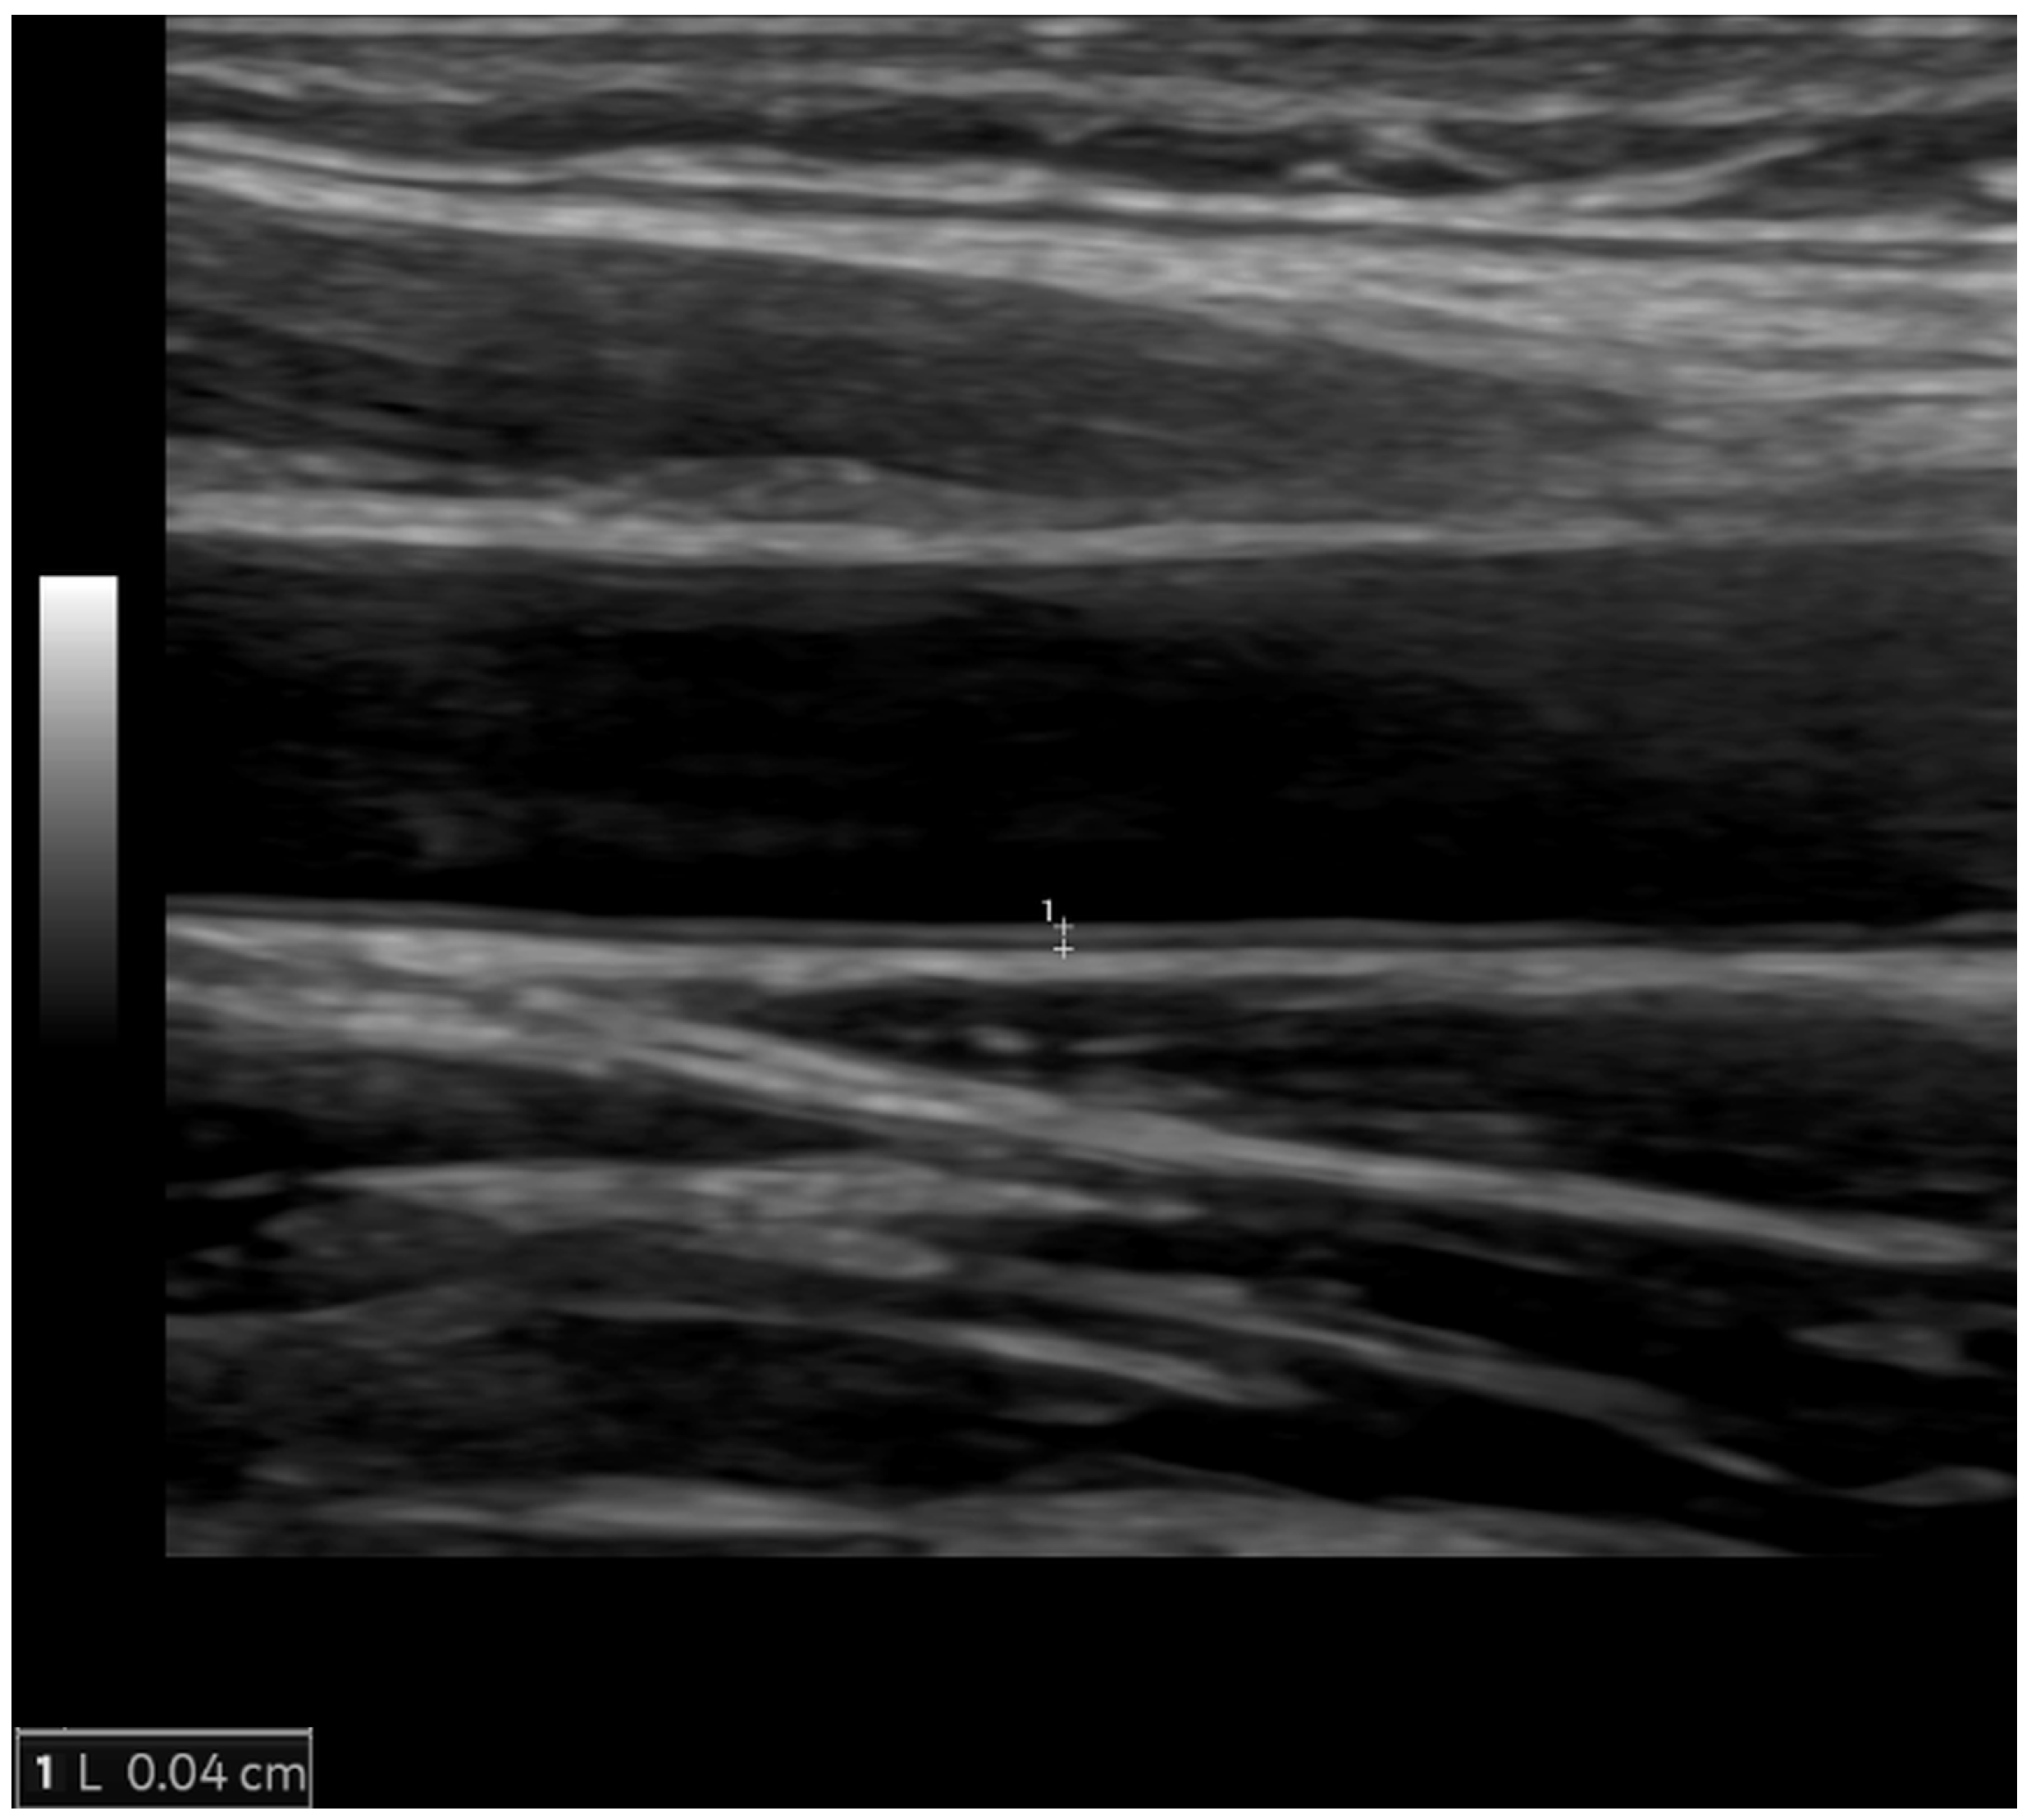

Carotid IMT (Figure 3) is a structural measure of vascular age that can be used for advanced cardiovascular risk assessment. It is not synonymous with atherosclerosis, but it can detect early stages of vascular aging. Carotid IMT refers to the combined thickness of the intimal and medial layers of the arterial wall, typically measured using high-resolution B-mode ultrasound on the far wall of the common carotid artery. It should be measured using a linear-array transducer that operates at a fundamental frequency of at least 7 MHz. As per the consensus from the American Society of Echocardiography, carotid IMT should be measured bilaterally at the far wall of the distal common carotid artery within a 1-cm-long straight segment just before the carotid bulb and compared with values from a normative dataset [46]. Cardiovascular risk increases progressively with rising IMT, but an IMT value of 0.9 mm is generally considered abnormal [27]. To enhance sensitivity in detecting subclinical atherosclerosis, carotid IMT measurement should be complemented by a comprehensive scan of the extracranial carotid arteries to check for the presence of carotid plaques. Atherosclerotic plaques are defined as a focal wall thickening at least 50% greater than that of the surrounding vessel wall or as a focal region with IMT greater than 1.5 mm that protrudes into the lumen and is distinct from the adjacent boundary. It is a non-invasive, relatively inexpensive test, feasible in all individuals and larger populations using portable, user-friendly ultrasound equipment after very short training of a sonographer. One of the major issues regarding carotid IMT is the standardization of measurement and the requirement for a formal educational program with hands-on training and follow-up of the examiners [46]. Compared to CAC, carotid IMT is a stronger predictor of stroke (multivariable-adjusted hazard ratio of 1.3 for IMT and 1.1 for CAC) but a weaker predictor of coronary disease (multivariable-adjusted hazard ratio of 1.2 for IMT and 2.5 for CAC) [47]. A meta-analysis of 14 population-based cohorts contributing data for 45,828 individuals showed that the addition of carotid IMT measurements to the Framingham Risk Score was associated with a small improvement in 10-year risk prediction of first-time myocardial infarction or stroke (0.8%; 95% confidence interval, 0.1–1.6%), and that this improvement is unlikely to be of clinical importance [48]. According to the current 2019 ACC/AHA Guideline on the Primary Prevention of Cardiovascular Disease and 2021 ESC Guidelines on cardiovascular disease prevention in clinical practice, it is not recommended as a risk assessment tool in clinical practice due to the lack of methodological standardization and the absence of added value of IMT in predicting future cardiovascular events [3,28]. However, carotid artery plaque assessment using ultrasonography may be considered a risk modifier when a CAC score is not feasible [3]. A carotid IMT >0.9 mm or the presence of a carotid plaque is considered to be a marker of asymptomatic target organ damage that is used for risk stratification among patients with arterial hypertension [27]. Carotid plaque and high IMT are independently associated with higher atherosclerotic cardiovascular disease risk in young adults in multivariate models [49]. Clinical tools integrating carotid IMT within global risk scoring systems are not available.

Figure 3.

The normal value of carotid intima-media thickness of 0.4 mm (between the calipers) in a young male individual.